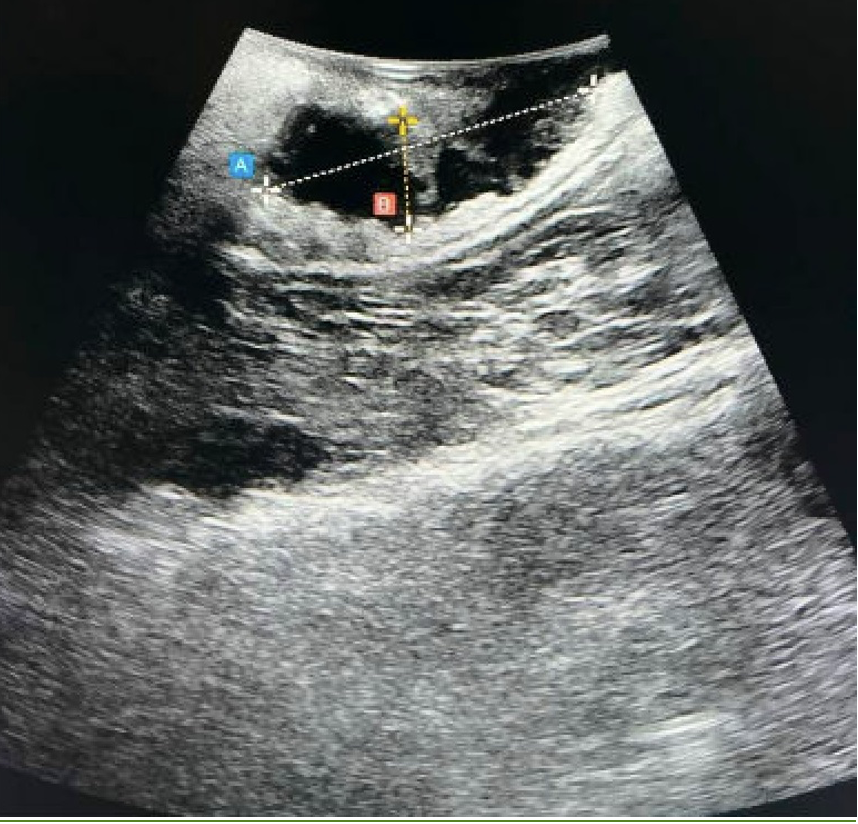

Intraoperative ultrasound image of rectosigmoid deep infiltrating endometriotic nodule.